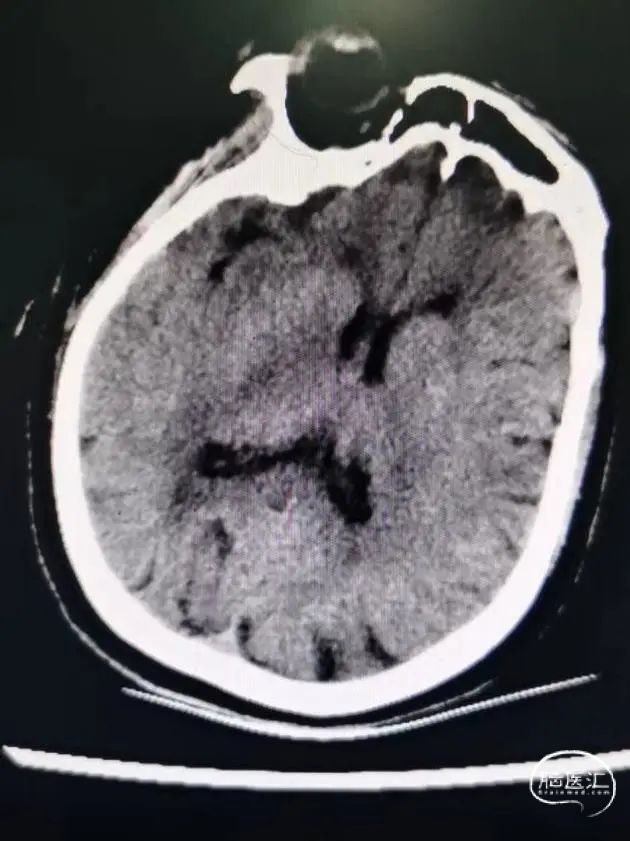

现病史:1小时前患者被家属发现意识不清,呼之不应,无发热、恶心呕吐、肢体抽搐等,急诊入院,头CT排除出血,心电图提示房颤心律。

术前影像学资料

患者系缺血性卒中,在静脉溶栓时间窗内,排除禁忌症,给予阿替普酶静脉66.6mg溶栓,术前NIHSS 40分,mRS 4分,并完善头颈CTA,提示右侧颈内动脉闭塞,结合心电图,考虑心源性栓塞,建议急诊血管内治疗,结合辅助检查,考虑血栓负荷量较大,首选治疗方案为支架取栓,备选导管抽栓。